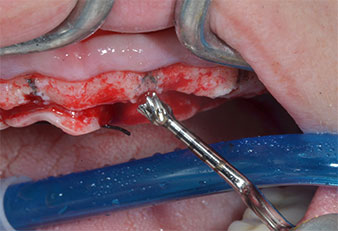

Para marcar las posiciones del implante y realizar la preparación piloto, se utilizó un inserto piezoeléctrico (Piezomed I1) con revestimiento de diamante y forma de llama (figura 3). Se tomaron precauciones para realizar movimientos hacia arriba y hacia abajo, con una potencia reducida, una irrigación completa y una baja presión (por debajo de 300 g). A continuación, se aplicó un inserto piloto (Piezomed I2A/I2P) para aumentar el diámetro inicial de 2 mm de los sitios de implante (figura 4), seguido de un inserto de 3 mm (Fig. 5).

Marcador ultrasónico Piezomed

Fig. 3: La preparación con inserto marcador ultrasónico Piezomed I1 se realizó con movimientos hacia arriba y hacia bajo, paralelos al eje longitudinal del área de trabajo.

Insertos Piezomed

Fig. 4: El siguiente paso fue el aumento piloto con los insertos I2A/I2P, que se aplicaron con un movimiento rotatorio horizontal.